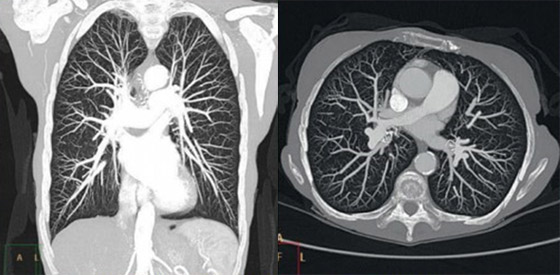

Iterative model reconstruction

With a SmartPath upgrade you can benefit from our advanced reconstruction technology – IMR, or iterative model reconstruction.

IMR allows you to combine virtually noise-free images and industry-leading low-contrast resolution with significantly lower doses[1]. And reconstruction time for the majority of reference protocols is less than 3 minutes*.

High image quality with reduced artifacts

Together iDose4 and O-MAR produce high image quality with reduced artifacts

iDose4 Premium Package is an innovative solution that helps you personalize image quality based on your patients’ needs at low dose. iDose4 improves image quality* through artifact prevention and increased spatial resolution at low dose. It provides a unique approach to managing important factors in patient care – low energy, low dose, and low injected contrast imaging. O-MAR reduces artifacts caused by large orthopedic implants. Together they produce high image quality with reduced artifacts for increased diagnostic confidence. In fact the majority of our reference protocols can be reconstructed in less than one minute.